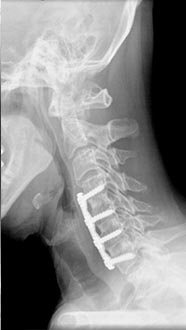

50 year old man presenting with left biceps and triceps weakness with numbness in his hand.

C6 corpectomy with complete resolution of the weakness and numbness.